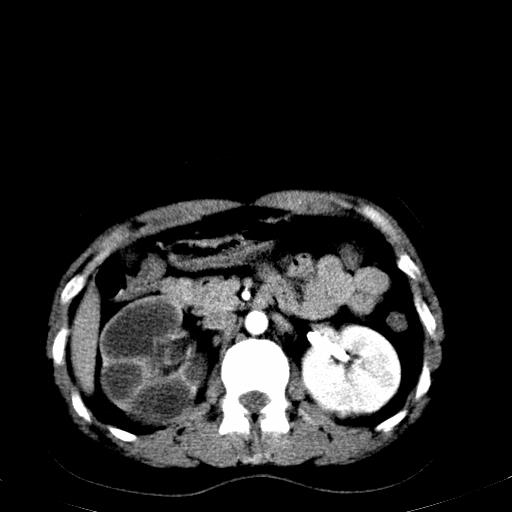

右肾多发囊肿,左肾、左输尿管结石

右肾重度积水,以肾盏积水明显,有分隔,上段输尿管轻度扩张,管壁增厚,考虑肾结核可能,请结合尿检查,胸部拍片排除肺结核。

左肾不像是结石吧,是不是做过造影啊

左肾哪里有结石???

左肾不是结石,是造影后改变.右肾积水,功能仅存.

右肾积水、左侧肾脏结石,建议进一步检查原因除外左肾结核可能